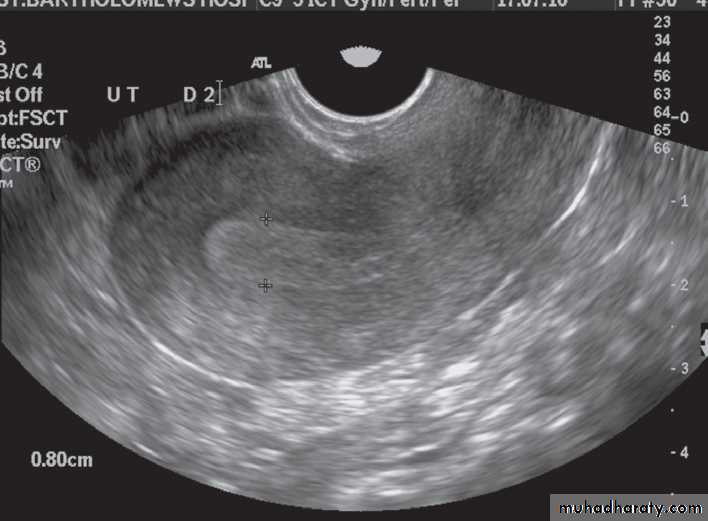

-The typical features of

polycystic ovaries on

ultrasound or MRI include

large volume ovaries

with multiple small

follicles arranged

around the periphery,

forming the appearance

of a ‘string of pearls’ .